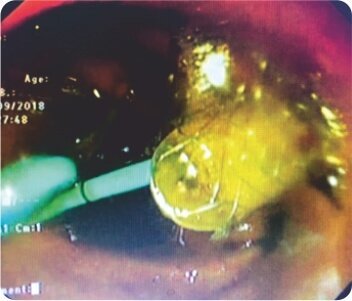

লিভারের দ্বিতীয় অংশে IHBRD এর EUS নির্দেশিত পাংচার পাকস্থলী থেকে করা হয়েছিল এবং কোলাঞ্জিওগ্রামের পরে, সিস্টোটোম ব্যবহার করে ট্র্যাক্টটি 10F পর্যন্ত ধারাবাহিকভাবে প্রসারিত করা হয়েছিল এবং পেট এবং লিভারের দ্বিতীয় অংশের সাথে সংযোগকারী একটি 60×10 মিমি সম্পূর্ণরূপে আবৃত বিলিয়ারি ধাতব স্টেন্ট স্থাপন করা হয়েছিল। ধাতব স্টেন্টের স্থানচ্যুতি রোধ করার জন্য ধাতব স্টেন্টের ভিতরে একটি 7F 7 সেমি ডাবল পিগটেল প্লাস্টিক স্টেন্ট স্থাপন করা হয়েছিল। কোনও পেরিপ্রোসিডেরাল জটিলতা ছিল না এবং বিলিরুবিনের স্বাভাবিকীকরণের পরে রোগীকে কেমোথেরাপি করা হয়েছিল। পদ্ধতির 3 মাস পরে ফলো-আপের সময়, রোগীর LFT স্বাভাবিক ছিল।

সিস্টোটোমের সাথে ট্র্যাক্টের প্রসারণ